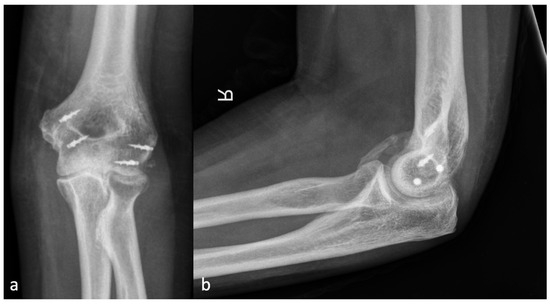

Figure 5.

(a) shows the AP and (b) shows the lateral X-ray with a brace formation radio-ulnar and represents an HO 4.